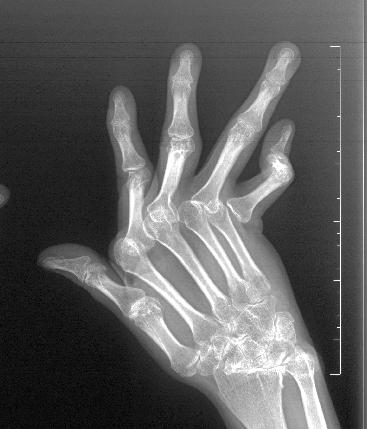

之后,李女士因间歇性停药导致病情反复,关节肿痛如影随形。更令人揪心的是,双手关节开始变形,掌指关节半脱位、手指向尺侧偏斜,原本灵活的指尖逐渐变成了“鹅颈样畸形”。严重的关节畸形让她不得不放弃工作,生活被无助与自卑层层包裹。

畸形复杂且差异大,患者可能同时存在“纽扣样畸形”“鹅颈样畸形”“尺偏畸形” 等多种问题,成品假体无法匹配;关节微环境复杂,长期炎症导致滑膜炎、肌腱损伤,关节周围免疫微环境复杂,给假体植入和稳定带来巨大挑战;传统假体缺陷明显,临床使用的硅胶假体,普遍存在硬度不足、易松动,甚至可能引发 “硅胶假体性滑膜炎”,长期效果差强人意;围手术期风险高,患者因长期服用免疫抑制剂,如何平衡炎症控制与手术安全,是必须攻克的难关。